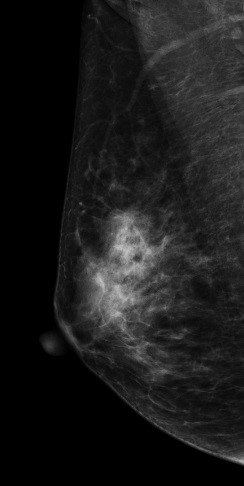

病史:患者43岁,发现右乳包块2周。

DBT图像:

常规2D图像MLO位上象限见一团块状影,在CC位上并没有发现可疑异常密度影,在V-Preview图像和tomo图像上我们可以清楚发现病变边界不清见长短不一毛刺,呈星芒样改变。

右乳上方略偏外局限致密影BI-RADS 4B 。

在TOMO图像上对星芒样病灶周边情况显示明显优于2D图像,最后病理证实右乳浸润性导管癌。